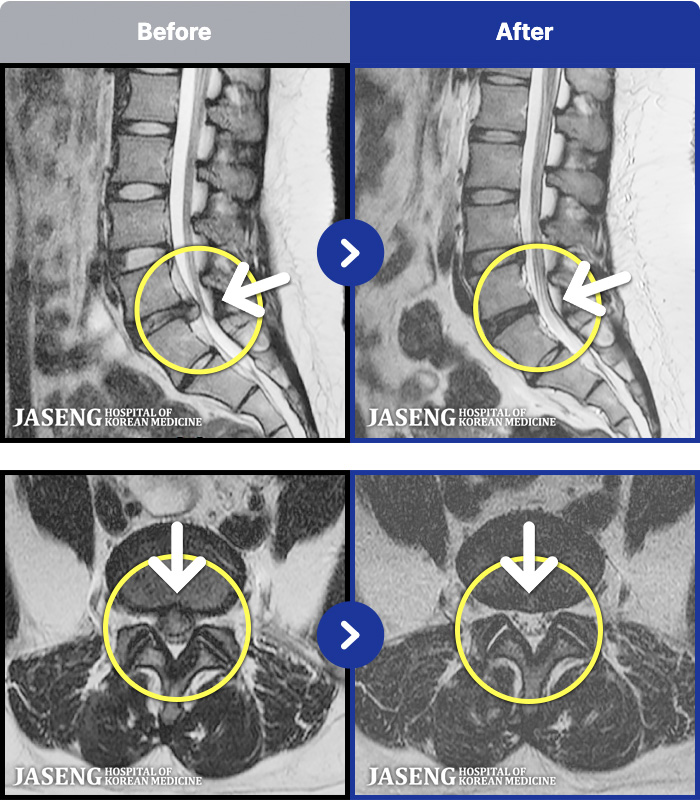

- MRI ġ

MRI ġ

1,240 MRI ũ ʸ Ȯϼ.